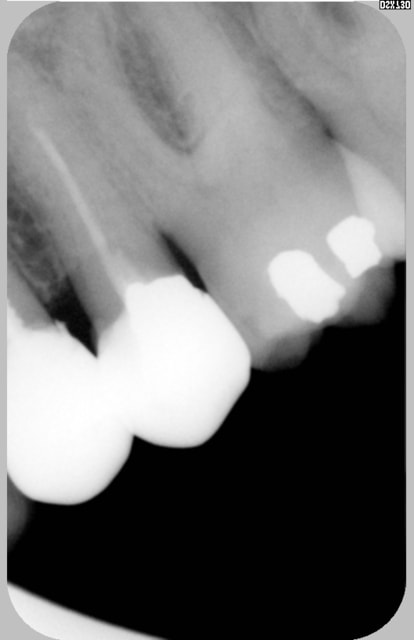

Pour un patient vivant dans la Caraibe cherche endo exclusif du coté de St Malo Rennes pour traiter une 26 infectée et calcifiée